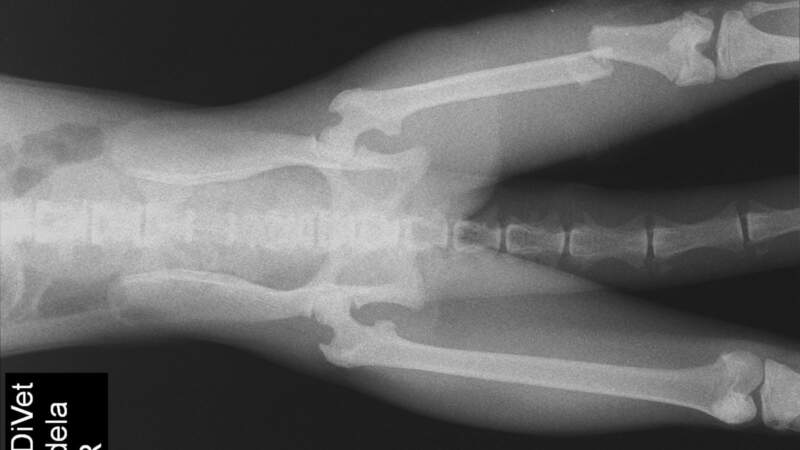

La mona ingresó con una fractura expuesta de fémur, lesión de alta complejidad en la que el hueso se quebró y perforó tejido antes de reingresar, generando un cuadro crítico. Tras su evaluación clínica inicial, el equipo profesional procedió a su estabilización con fluidoterapia y medicación específica. Una vez compensada, se programó y realizó una cirugía traumatológica en la que se colocó una placa y cuatro tornillos para reparar la fractura.

La intervención fue llevada adelante por un equipo de profesionales especializados, consolidando la capacidad técnica del Parque para abordar este tipo de emergencias en fauna silvestre. Posteriormente, el ejemplar permaneció varios días en reposo absoluto, bajo tratamiento con analgésicos y antibióticos, con controles periódicos cada 12 horas.